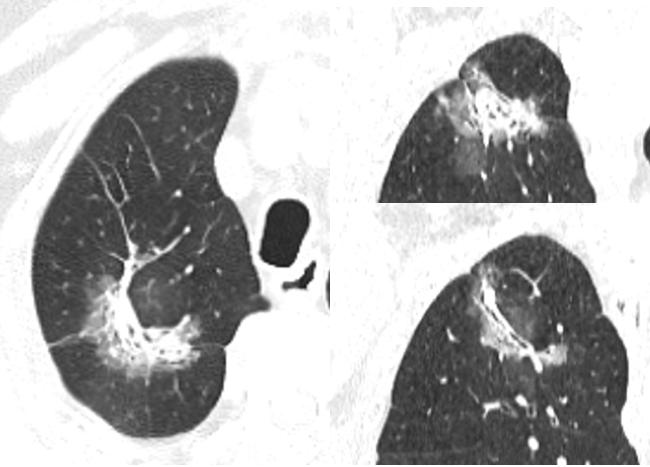

病例二

病史:女性,70岁。主诉:查体发现右肺上叶占位1周余。

影像描述:右肺上叶尖段见一不规则形混合磨玻璃密度灶,大小约 .7X4.2X4.5m,内可见多发小空腔中央部分较密实,周边可见斑片状密度增高影及毛刺,边界不清,邻近胸膜受牵拉,增强扫描实性成分可见强化:双肺另见多发点状结节灶,边界尚清,增强扫描未见明显强化。左肺上叶舌段见条索状密度增高灶,邻近胸膜受牵拉。段及以上支气管通畅。食管胸下段、胃责门及小弯侧胃壁略显增厚。纵隔内未见异常增大的淋巴结。双侧胸腔未见明显液性密度灶。

影像诊断:右肺上叶混合磨玻璃灶,鉴别于肺癌与机化性肺炎,建议病理学检查:双肺多发点状结节灶,建议随诊复查:

病理:腺癌。

发炎:混合磨玻璃,周边毛刺,胸膜牵拉。感觉还是先抗炎观察再说呗。倾向不好的东西。